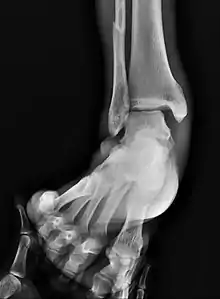

Surgically fixated bimalleolar ankle fracture

The broad goals of treating ankle fractures are restoring the ankle joint to normal alignment, healing the fracture, and preventing arthritis.[8] The stability of the ankle joint often dictates treatment. Certain fracture patterns are stable and are thus treated without surgery similarly to ankle sprains. Unstable fractures require surgery, most often an open reduction and internal fixation (ORIF), which is usually performed with permanently implanted metal hardware that holds the bones in place while the natural healing process occurs. A cast or splint will be required to immobilize the ankle following surgery.[11] Stable ankle fractures with preserved joint alignment may be treated with non-operative measures (splinting, casting, and/or walking boot).[11]